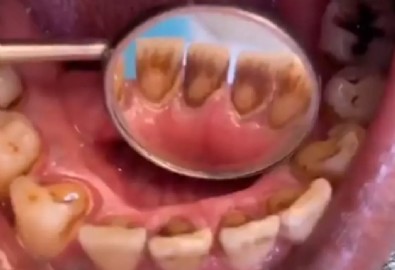

TikTok hesabından paylaştığı videoda bir hastanın ağzının içini gösteren Dr. Maryam Hadian, “'sigara içenlerin dişleri' böyle görünüyor” dedi. TikTok'ta yayınlanan videoda, her dişte koyu kahverengi lekelenme görülüyor, ön alt kısımdaki iki arka kısım neredeyse tamamen kaplanmış durumda. Doktorun paylaştığı video yarım milyondan fazla beğeni aldı.

Tütündeki nikotin ve katranın dişleri çok kısa sürede sarardığı ve çok sigara içenlerin yıllarca sigara içtikten sonra dişlerinin kahverengi veya griye döndüğünü görebileceği iyi bilinmektedir.